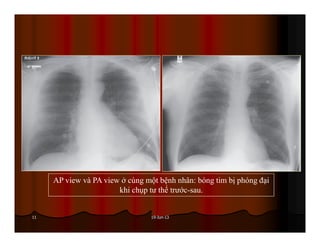

AP view và PA view ở cùng một bệnh nhân: bóng tim bị phóng đại

khi chụp tư thế trước-sau.

19-Jun-1311 AP view vàPA view ở cùng một bệnh nhân: bóng tim bị phóng đại khi chụp tư thế trước-sau.